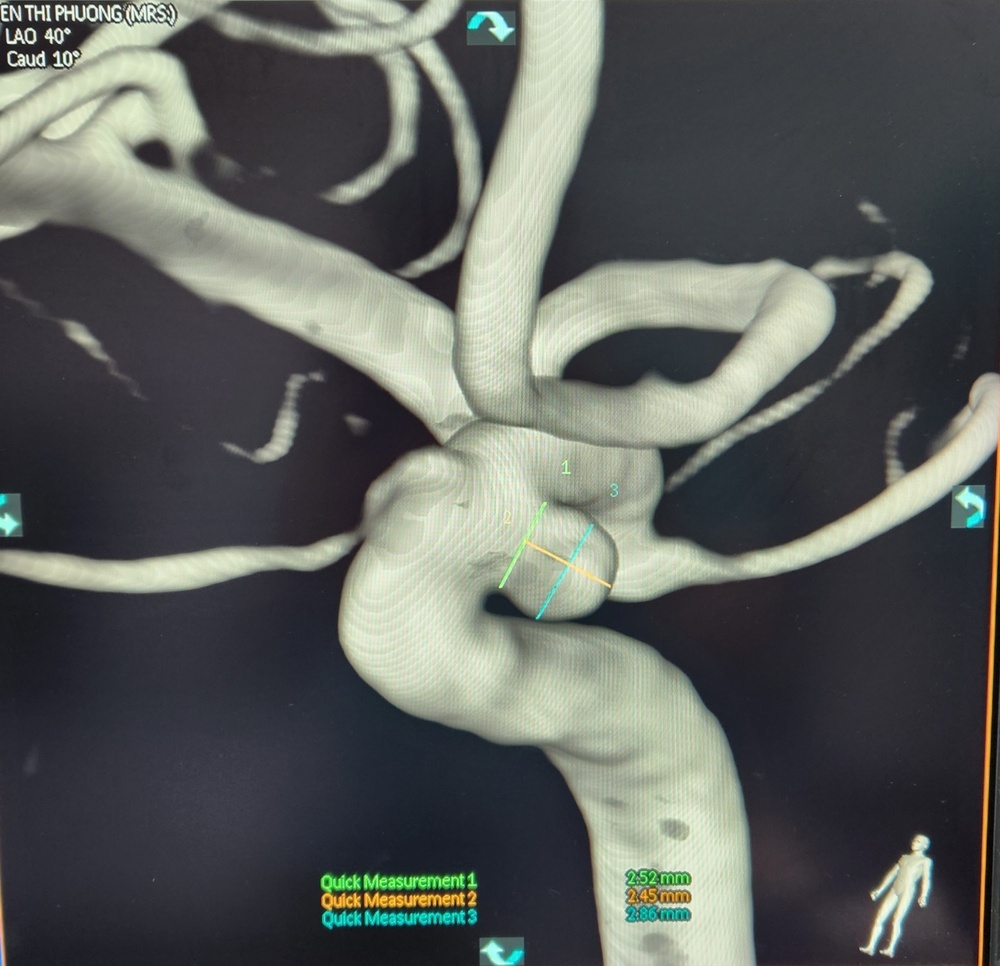

Qua kết quả chụp MRI sọ não của chị P., bác sĩ chuyên khoa I Nguyễn Minh Đức, khoa Ngoại Thần kinh và Can thiệp nội mạch thần kinh, phát hiện có túi phình mạch máu não ở động mạch cảnh trong, bên phải. Túi phình lớn dần qua các lần theo dõi.

Kết quả chụp phim DSA cho thấy động mạch cảnh của bệnh nhân có túi phình lớn.

Chị P. được đề nghị chụp mạch số hóa xóa nền (DS). Kết quả cho thấy túi phình trong não lồi hẳn lên thành mạch.